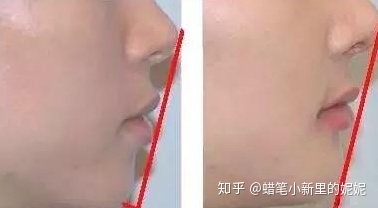

你可以用直尺子连接鼻尖-上嘴唇-颏(两腮和嘴的下面)试一下。

正常的三点应该是在一条直线上,假如这三点没有连成一条线,通常是两腮和嘴的下面没在同一条线上,就说明你的美学线不正常。

左图下颌后缩,上颌前突 右图为正常下巴

说明你存在上颌前突,下颌后缩等问题,而美学线不好看则直接影响了整个面部侧面的美观。